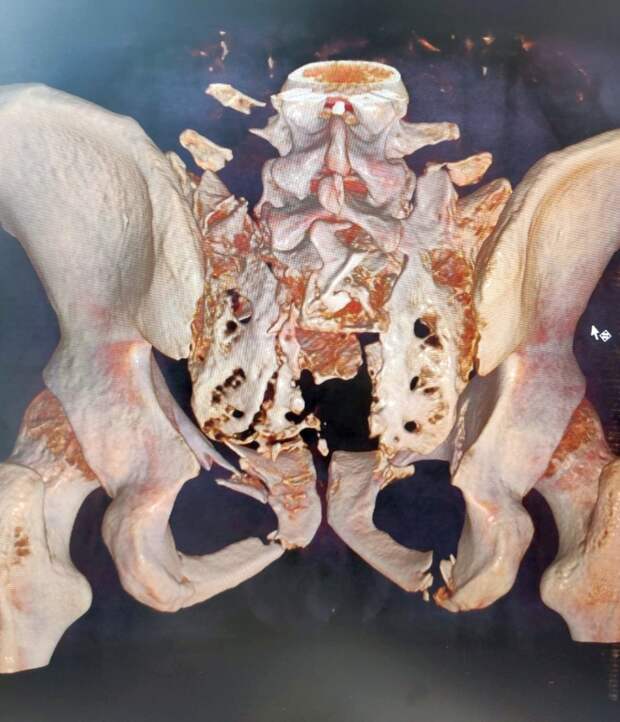

С множественными травмами пациента сначала доставили в Областную больницу № 3 г. Тобольска. Кости таза были настолько разрушены, что, по сути, таз был «оторван» от позвоночника. Врачи компенсировали состояние, выполнили первичную стабилизацию костей аппаратами внешней фиксации.

Пациент не мог пошевелиться из-за отсутствия опорной функции мышц спины и живота, ситуацию усугубляло повреждение нервных образований в раздробленном крестце. Тобольские специалисты приняли решение перевести его в Курган.

«Нами была проведена реконструкция повреждений тазового кольца. На первом этапе операции мы выполнили замену аппарата первичной фиксации, наложенного в Тобольске, далее осуществили закрытую репозицию положения костей таза относительно позвоночного столба и его фиксацию в достигнутом положении с помощью специальных тазовых винтов. Следующим этапом операции был домонтаж аппарата таза до кольцевой опоры и соединение его с позвоночником. Таким образом «привязали» таз к позвоночному столбу», — объяснил руководитель Клиники реконструктивной хирургии повреждений конечностей и таза Центра Илизарова, к. м. н. Алексей Гринь.